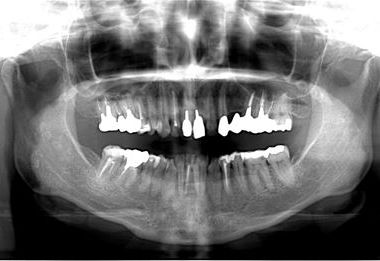

| 性別/年齢 | 女性 / 40歳 | ||||||||||||||||||||||||||||||||

| 治療方針 | 保存不能な歯を抜歯し、セラミック治療にて、機能的・審美的回復を行う。 | ||||||||||||||||||||||||||||||||

| 治療内容 | ジルコニアフレームオールセラミッククラウン7本(オールセラミック用土台3本)、ハイブリッドセラミッククラウン1本、ハイブリッドセラミックインレー1本 | ||||||||||||||||||||||||||||||||